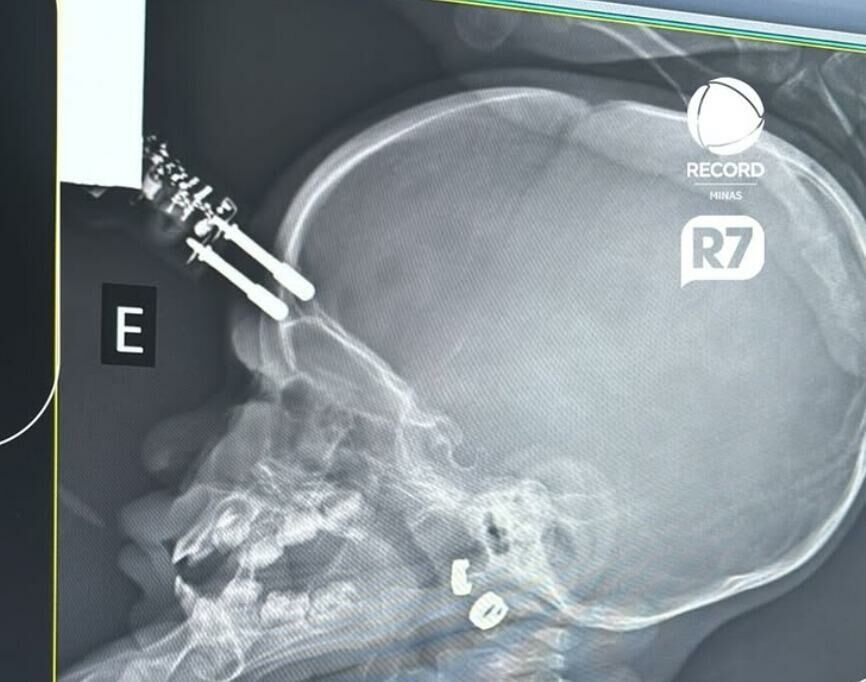

Uma menina de 1 ano e 4 meses precisou passar por cirurgia após um acidente doméstico em Divinópolis (MG), a cerca de 117 km de Belo Horizonte. A criança caiu da cama e teve um pino de carregador de celular cravado na testa, atingindo inclusive parte do cérebro.

Segundo relato do neurocirurgião Bruno Castro, responsável pelo atendimento, o caso ocorreu na última segunda-feira (12). A mãe da criança escutou o choro vindo do quarto e, ao chegar, encontrou a filha caída no chão, com sangramento e o objeto perfurando a região da cabeça. “Era um carregador de celular comum. Um dos pinos estava cravado, atravessando o crânio na região frontal da criança”, detalhou o médico.

Inicialmente, a menina foi levada para uma Unidade de Pronto Atendimento (UPA) da cidade. Diante da gravidade, foi transferida para o setor de urgência do Hospital São João de Deus, onde exames de imagem confirmaram a extensão do ferimento. “A tomografia mostrou que o pino estava machucando o cérebro, atingindo a ponta do lobo frontal”, explicou o médico.

De acordo com informações do portal R7 e da Record Minas, a criança foi rapidamente levada ao centro cirúrgico. “Foi uma cirurgia rápida, tranquila, sem intercorrências. Estancamos um pequeno sangramento e corrigimos a falha”, afirmou Bruno Castro.